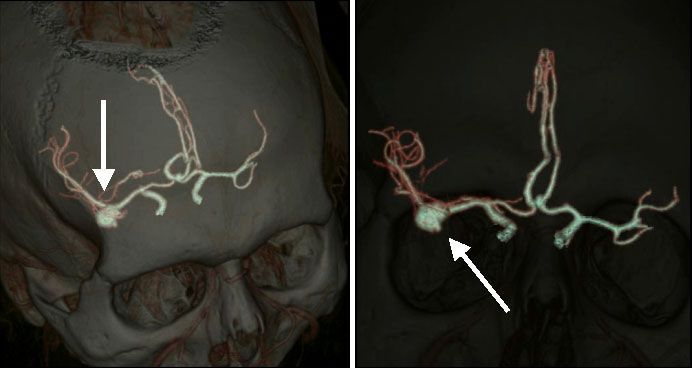

МСКТ экстра- и интракраниальных сосудов проводится при: сосудистом поражении головного мозга, нарушении мозгового кровообращения – это показания для изучения анатомии интракраниальных сосудов, сосудов шеи с целью исключения аномалий развития, в том числе выявление всевозможных мальформаций артерий (рис. №6-7), а также для исключения атеросклеротического поражения экстра - и интракраниальных артерий у больных, которые перенесли острое нарушение мозгового кровообращения или транзиторные ишемические атаки (рис №8) [2,3]. Одновременно с исследованием артерий проводится реконструкция анатомии головного мозга, с выявлением мельчайших повреждений (опухолей, гематом и т.д.), размером от 0,4-0,6 мм. Точная диагностика при МСКТ позволит определить причину заболевания, локализацию поражения, что необходимо для определения тактики дальнейшего лечения.

![]() |

| Рис.6-7. Диагностированная аневризма артерии при МСКТ интракраниальных артерий (стрелки). |